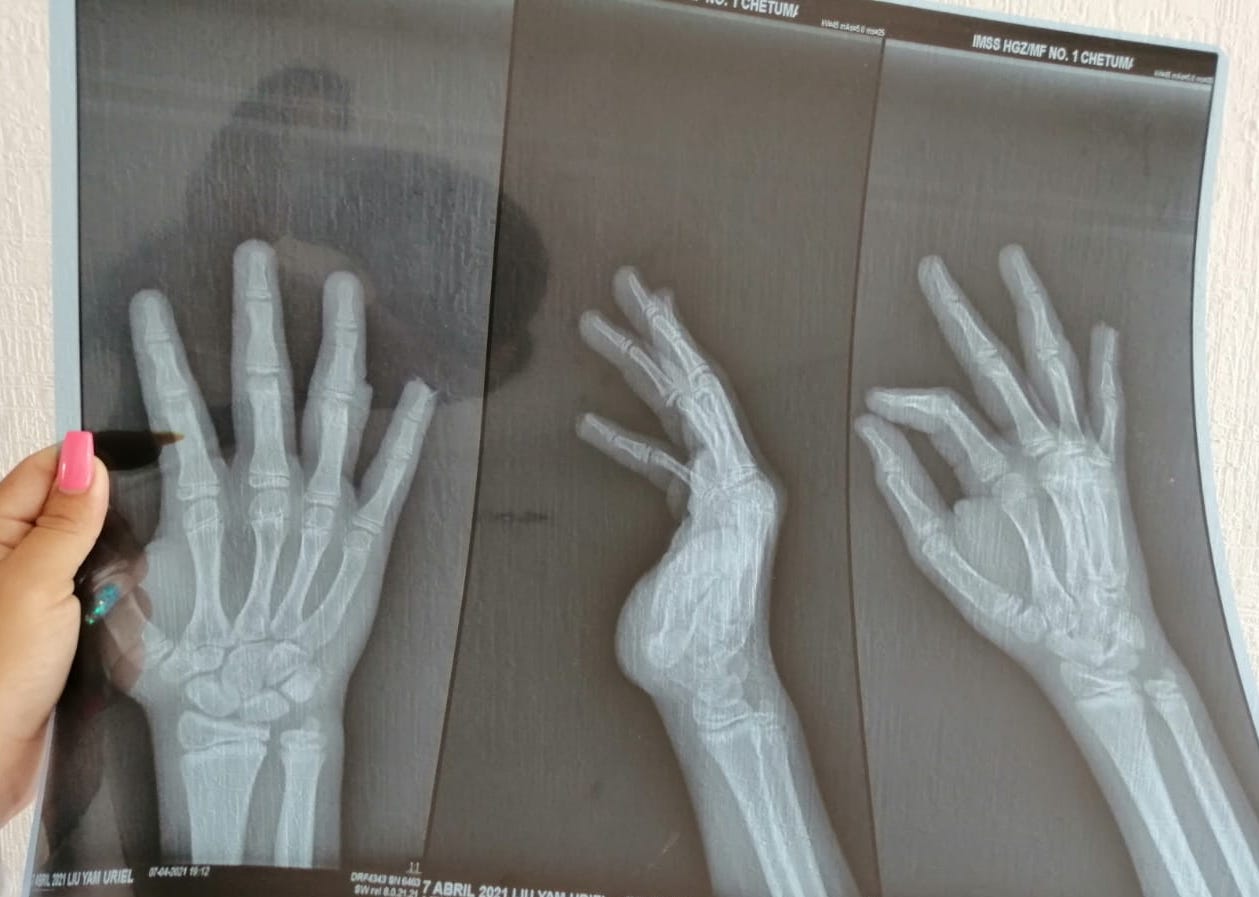

Y es que cuando estaba jugando en el parque o deberíamos llamarle “trampa mortal”, por las condiciones en las que se encuentra, que esta ubicado en la colonia Sian Kaan 2, el menor de 11 años de nombre Uriel iba pasando cuando una de las estructuras metálicas colapso y le aplasto la mano, situación que le provoco lesiones en el dedo meñique que incluso le arrancó la punta de su dedo y en el dedo anular de la mano derecha que casi se lo cercena

La madre del menor señaló que los médicos tuvieron que hacerle 3 cirugías, con un total de 11 puntadas para poder reconstruir ambos dedos del pequeño Uriel, además de que señaló es lamentable que las autoridades sigan siendo inútiles y desinteresadas, pues estos deberían estar dar mantenimiento de los parques para evitar este tipo de situaciones donde la vida de los menores peligra.